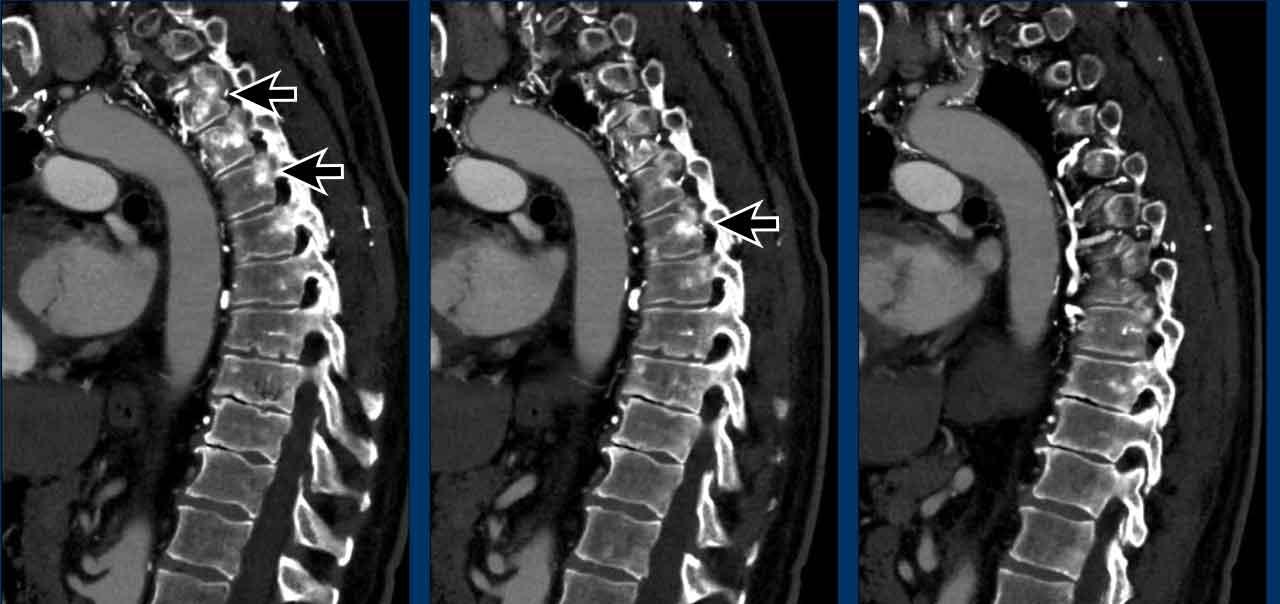

Các hình ảnh này của một bệnh nhân bị ung thư tuyến ức.

Lưu ý hoạt độ phóng xạ không đều ở ngoại vi tổn thương trên PET.

Khối u đã được phẫu thuật cắt bỏ.

Trong quá trình theo dõi, một CT được thực hiện.

Tiếp tục xem CT theo dõi…

Trên CT, phát hiện các cấu trúc tăng tỷ trọng mới trong các đốt sống (mũi tên).

Chúng không có trên CT trước đó.

Nhận định của bạn là gì?

Hãy phân tích hình ảnh trước rồi tiếp tục đọc.

Hình ảnh

Lưu ý sự hiện diện của các tĩnh mạch bàng hệ giãn. Điều này được giải thích bởi thực tế là trong phẫu thuật, tĩnh mạch tay đầu (brachiocephalic vein) bị thắt lại, có thể dẫn đến sự hình thành các tĩnh mạch bàng hệ đáng kể. Các cấu trúc tăng tỷ trọng quan sát thấy trong thân đốt sống không phải là di căn xơ cứng, mà là hậu quả của ứ trệ tĩnh mạch. Những hình ảnh này biểu hiện sự ngấm thuốc do ứ trệ tĩnh mạch, không phải bệnh di căn. Trên CT không tiêm thuốc cản quang, tình trạng tăng tỷ trọng này sẽ không quan sát được.

Tiếp tục xem phim theo dõi muộn hơn…

Trên phim theo dõi muộn hơn, tình trạng ứ trệ tĩnh mạch không còn quan sát thấy nữa.